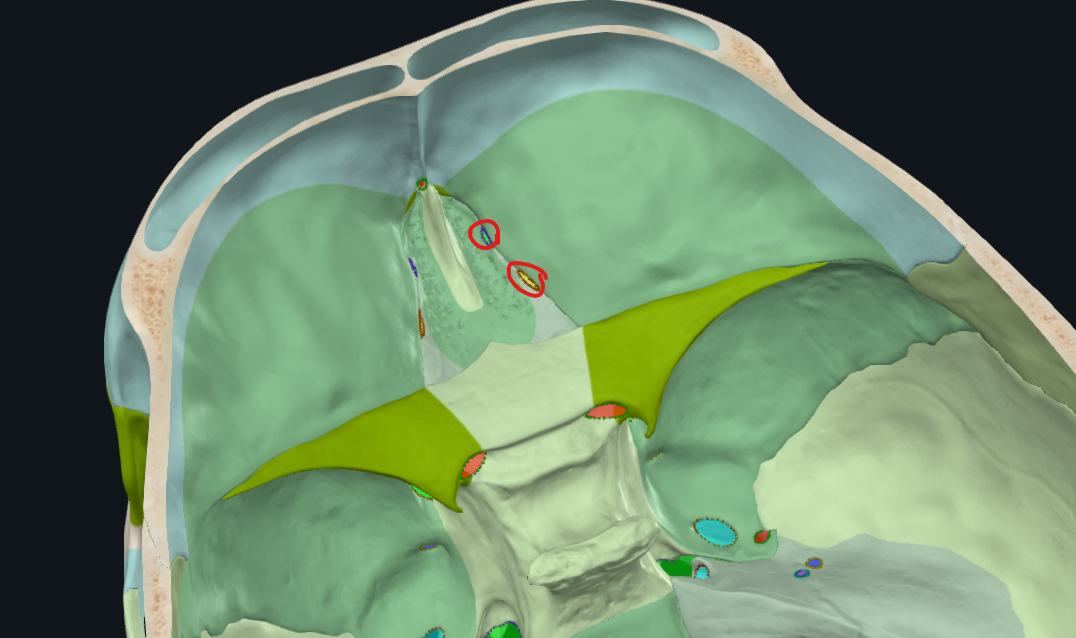

Agujeros etmoidales

Anterior y posterior

Dos apófisis alares que articulan con el frontal, creando el foramen cecum

Foramen Caecum

Llamado también Agujero Ciego

Lámina cribosa del etmoides

Forma parte del piso de la fosa craneal anterior

Perforada por múltiples orificios, por eso el nombre de cribiforme

Apófisis crista galli

Triangular, borde anterior bajo articula con el hueso frontal y completan el agujero ciego(foramen cecum) entre surcos

Hueso esfenoides

Cara posterior del Etmoides